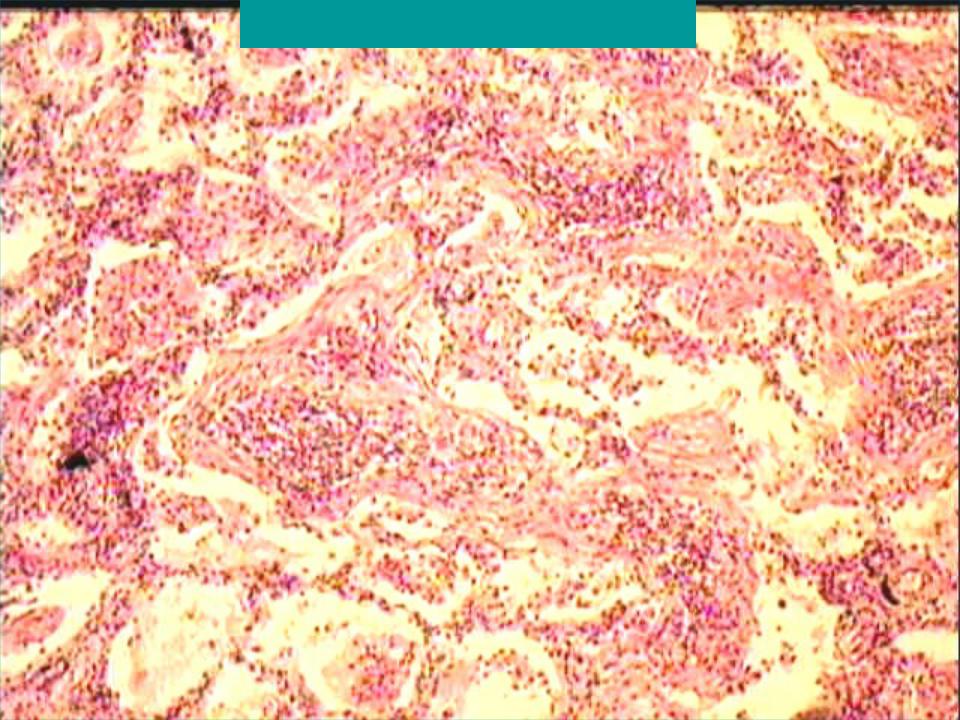

Карнификация Легкого: Микропрепараты и Диагностика

Раздел: Калейдоскоп образов